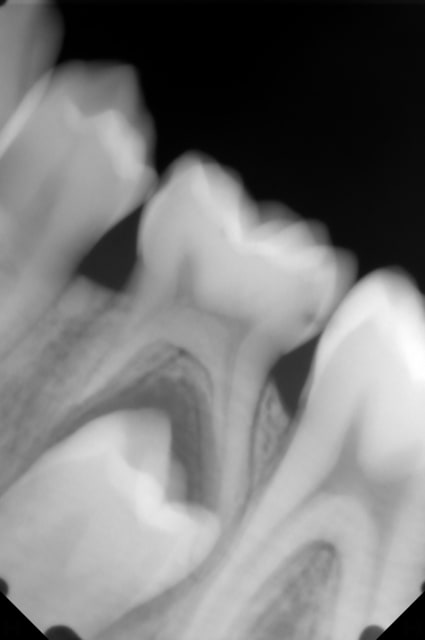

Aujourd'hui j'ai reçu un garçon de 13ans, toutes les dent temporaires sont tombées sauf la 75, j'ai fait une radio et la 35 est présente, sauf que la 75 n'a pas commencé sa rhizalyse semble-t-il.

Je pensait extraire la 75 pour "stimuler" l'éruption de la 35, qu'en pensez-vous?

Je joint la rétro de la 75/35 et de la 45 pour que vous visualisiez l'édification radiculaire.

Si l'édification radiculaire du germe de 35 est égale ou sup à 2/3 alors l'extraction de la dent temporaire accélère l'éruption du germe. Sinon ralentissement de l'éruption.

- Au vu de l’édification radiculaire de la 45 (2/3) et en considérant que celle de la 35 est symétrique, il est temps d'avulser la 75.